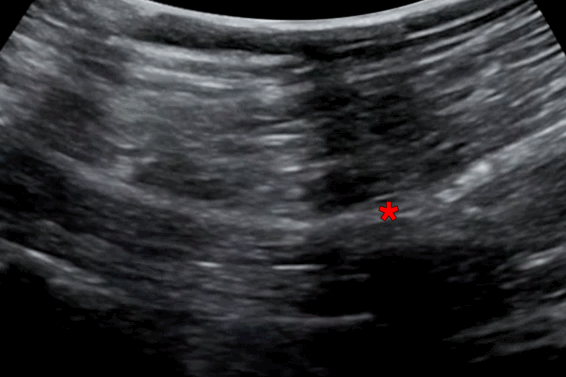

Transgluteal Sciatic